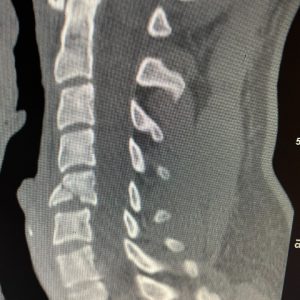

As a Neurosurgeon, spinal fractures of the neck from diving accidents are things that I see way too often. This young man dove from a boat into shallow water. He presented with some numbness in his arm and hand.

He had a fracture with the instability of his cervical spine at C5, requiring anterior and posterior surgery to decompress the nerve roots and stabilize his unstable cervical spine. He was lucky! His numbness improved, and he made a full recovery.